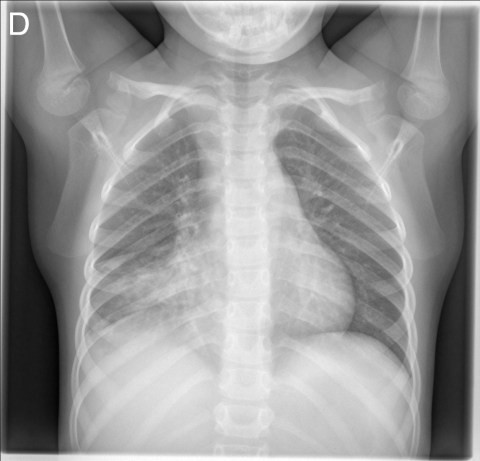

Solución: Es un estudio Normal. Silueta cardiomediastínica y parénquimas pulmonares sin alteraciones significativas.

CASO: sospecha de neumonía.

Hallazgos:

- En un principio podríamos decir que existe un aumento de densidad retrocardiaco que podría ser compatible con condensación neumónica a dicho nivel, sin embargo estamos ante una placa poco inspirada, lo cual puede llevarnos a cometer errores diagnósticos.

- Se recomendó volver a realizar la radiografía, observar a continuación:

Ya no se observa el aumento de densidad retrocardiaco, la placa es normal.

INSPIRACIÓN: Una placa bien inspirada es aquella en la que se observar 6-7 arcos costales anteriores o 10-11 arcos costales posteriores. Lo contrario puede producir imágenes falsas de condensaciones o de seudocardiomegalia.